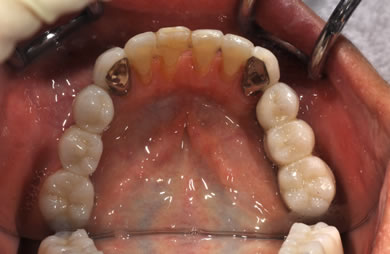

骨再生スピードインプラント治療+AGC連結セラミック治療

| 治療方針 | 上顎の歯周組織がかなり侵襲されているため、ソケットリフト法にて骨を回復させ、機能的回復だけでなく審美的回復も行うためにAGCハイブリッド連結ブリッジにて補綴処置を行う。 | ||||||||||||||||||||||||||||||||

| 治療内容 | インプラント12本(ソケットリフト+抜歯即日スピードインプラント)、ハイブリッドセラミック8本、AGCハイブリッドセラミック連結ブリッジ1装置、テンポラリーインプラント2本、遊離歯肉移植術 | ||||||||||||||||||||||||||||||||